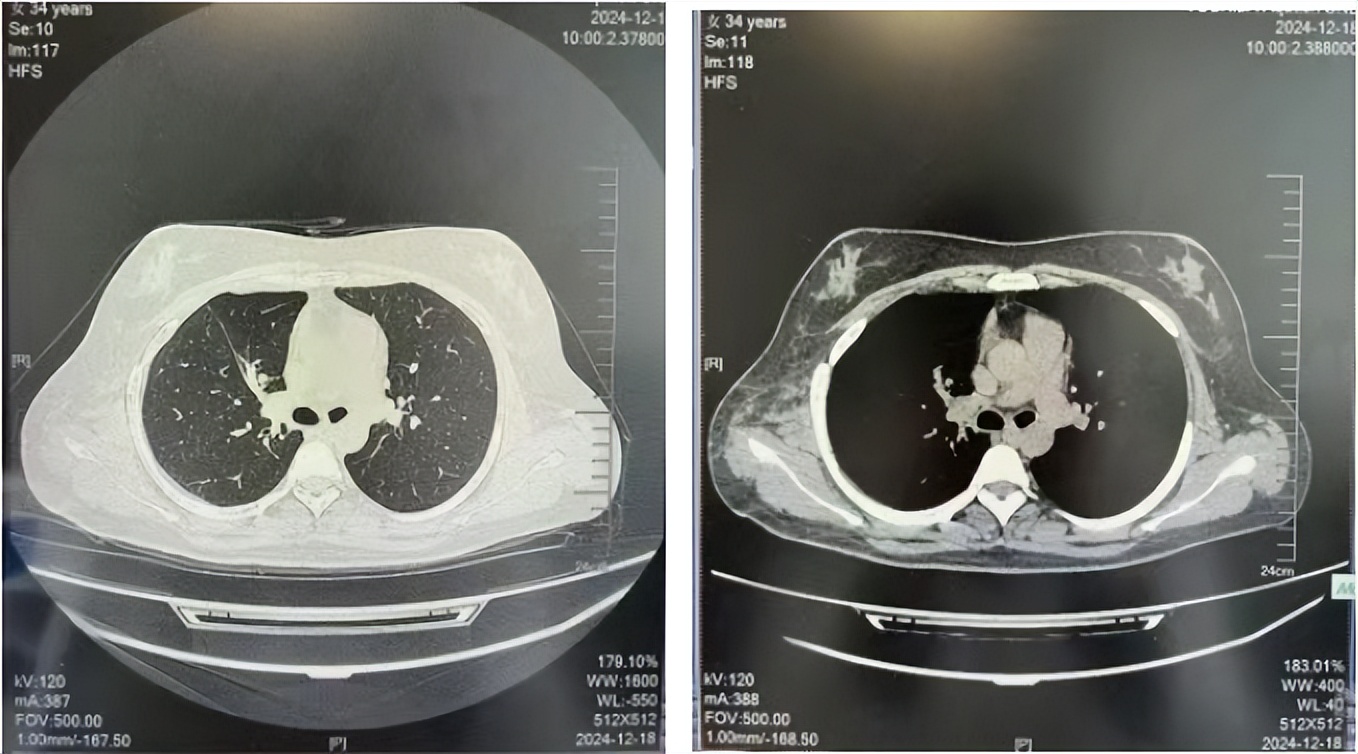

56岁,女性,无吸烟史饮酒史,既往体健。2023年02月患者体检发现肺占位性病变,胸部增强CT:右肺下叶后基底段结节;右侧锁骨上及纵隔内多发淋巴结肿大。PET-CT:右肺下叶周围型肺癌可能性大;1R、2L、3P、4R、4L及7组淋巴结转移可能性大。2023年02月就诊于本院胸外科行超声胃镜下纵隔肿物穿刺活检术,病理:结合免疫组化,符合肺腺癌。行NGS基因检测:EML4:exon20-ALK:exon20融合。PD-L1(克隆号22C3)TPS=55%。

治疗经过:2023年3月27日始行恩沙替尼靶向治疗至今,最佳疗效为PR,末次评效为维持PR。期间出现轻度肝功能异常(DILI 1级),对症处理后好转。截止目前PFS为26个月。

2023年2月20日基线检查

2024年6月复查PR(最佳疗效)

2024年12月复查维持PR

2025年3月复查维持PR